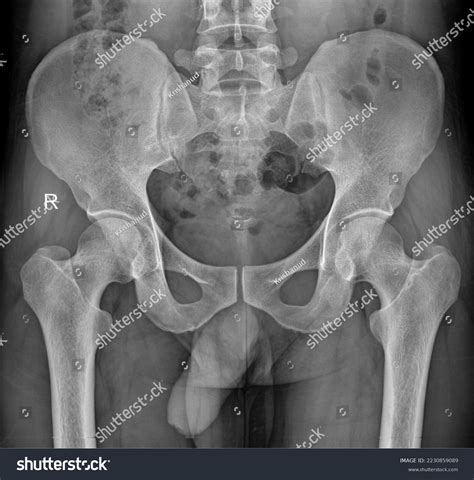

A Normal Hip X Ray is a radiographic image used to visualize the hip joint and surrounding structures. It helps in diagnosing a wide range of conditions, including fractures, dislocations, arthritis, and developmental abnormalities. The term โ€œnormalโ€ refers to the expected appearance of the hip joint in the absence of any pathological conditions.

Interpreting a Normal Hip X Ray

Interpreting a Normal Hip X Ray requires a trained eye. Radiologists look for specific features to determine the health of the hip joint. Key elements include: